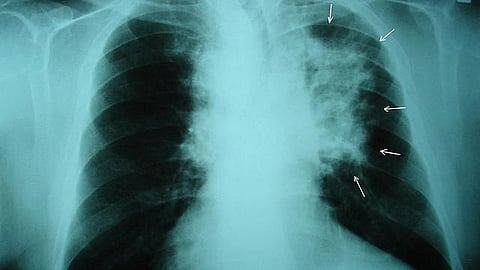

Lung cancer is the deadliest of all cancers. It grows quietly and is usually not detected until it has spread to other parts of the body. Early detection is key to survival, especially for someone at high risk like Buff, who is African American and has a history of smoking.

Although it is well documented that Black smokers develop lung cancer at younger ages than white smokers even when they smoke fewer cigarettes, the guidelines that doctors use to recommend patients for screening have been slow to reflect the disparity. If Buff had the same conversation with his doctor one year earlier, he would not have qualified for the CT scan that detected a nickel-sized growth on his left lung.

But a 2019 study published in JAMA Oncology found that under those parameters, 68% of Black smokers would have been ineligible for screening at the time of their lung cancer diagnosis, compared with 44 percent of white smokers. In 2021, the U.S. Preventive Services Task Force lowered the recommended screening age for lung cancer to 50 and reduced the number of pack years to 20.

A low-dose CT scan, for example, is one of the most powerful tools available for detecting lung cancer early and reducing deaths. But according to the 2022 Lung Health Barometer from the American Lung Association, nearly 70% of people don’t even know that type of screening is available. And according to Silvestri, only a small percentage of those who are eligible actually get screened.